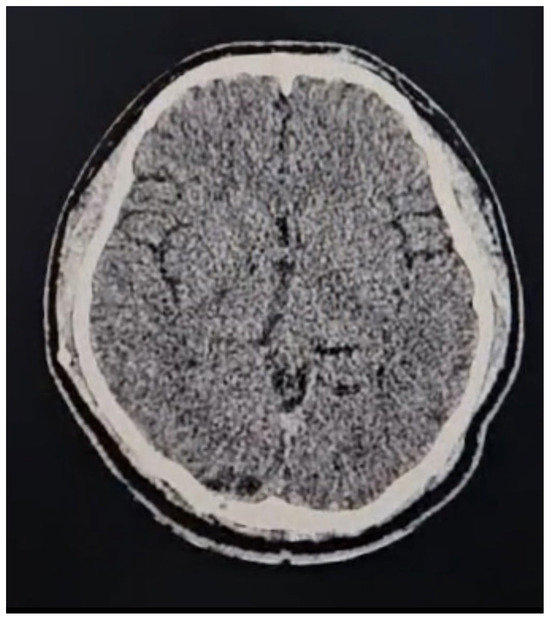

- Case 2: The AR-assisted transtentorial approach enabled near-total resection of a pineal region ependymoma, illustrating the technology’s efficacy in managing deep-seated tumors with complex vascular relationships; guided by AR to the pineal region where the tumor was located, in turn, AR allowed us to know the limits of the tumor; those limits were blocked to direct vision by the parenchyma and vascular structures (in-ferior sagittal sinuses, internal cerebral veins, basal of Rosenthal, vein of Galen, rectus, and inferior longitudinal sinus).